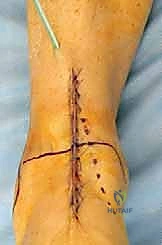

تُجرى العملية عادة تحت التخدير النصفي أو العام، وتستغرق حوالي الساعتين إلى ثلاث ساعات. الدقة هنا تقاس بالمليمترات وأجزاء الدرجة الزاوية.

1. الشق الجراحي والوصول للمفصل

يقوم الجراح بإجراء شق أمامي طولي (Anterior Approach) في منتصف الكاحل. يتم إبعاد الأوتار والأوعية الدموية والأعصاب بعناية فائقة (هنا تتجلى أهمية مهارات الجراحة الدقيقة التي يمتلكها الدكتور هطيف) للوصول إلى محفظة المفصل.